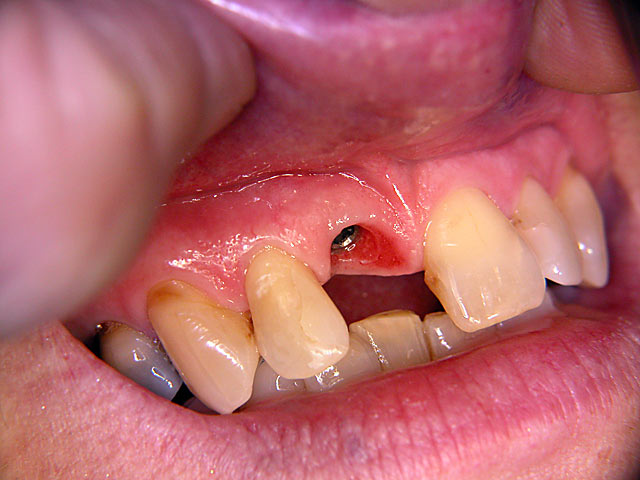

Die folgenden Patientenfälle sollen Ihnen einen Einblick in die Möglichkeiten der modernen Implantation geben.

Sofort-Implantation:

Implantation – Patientenbeispiel 2: